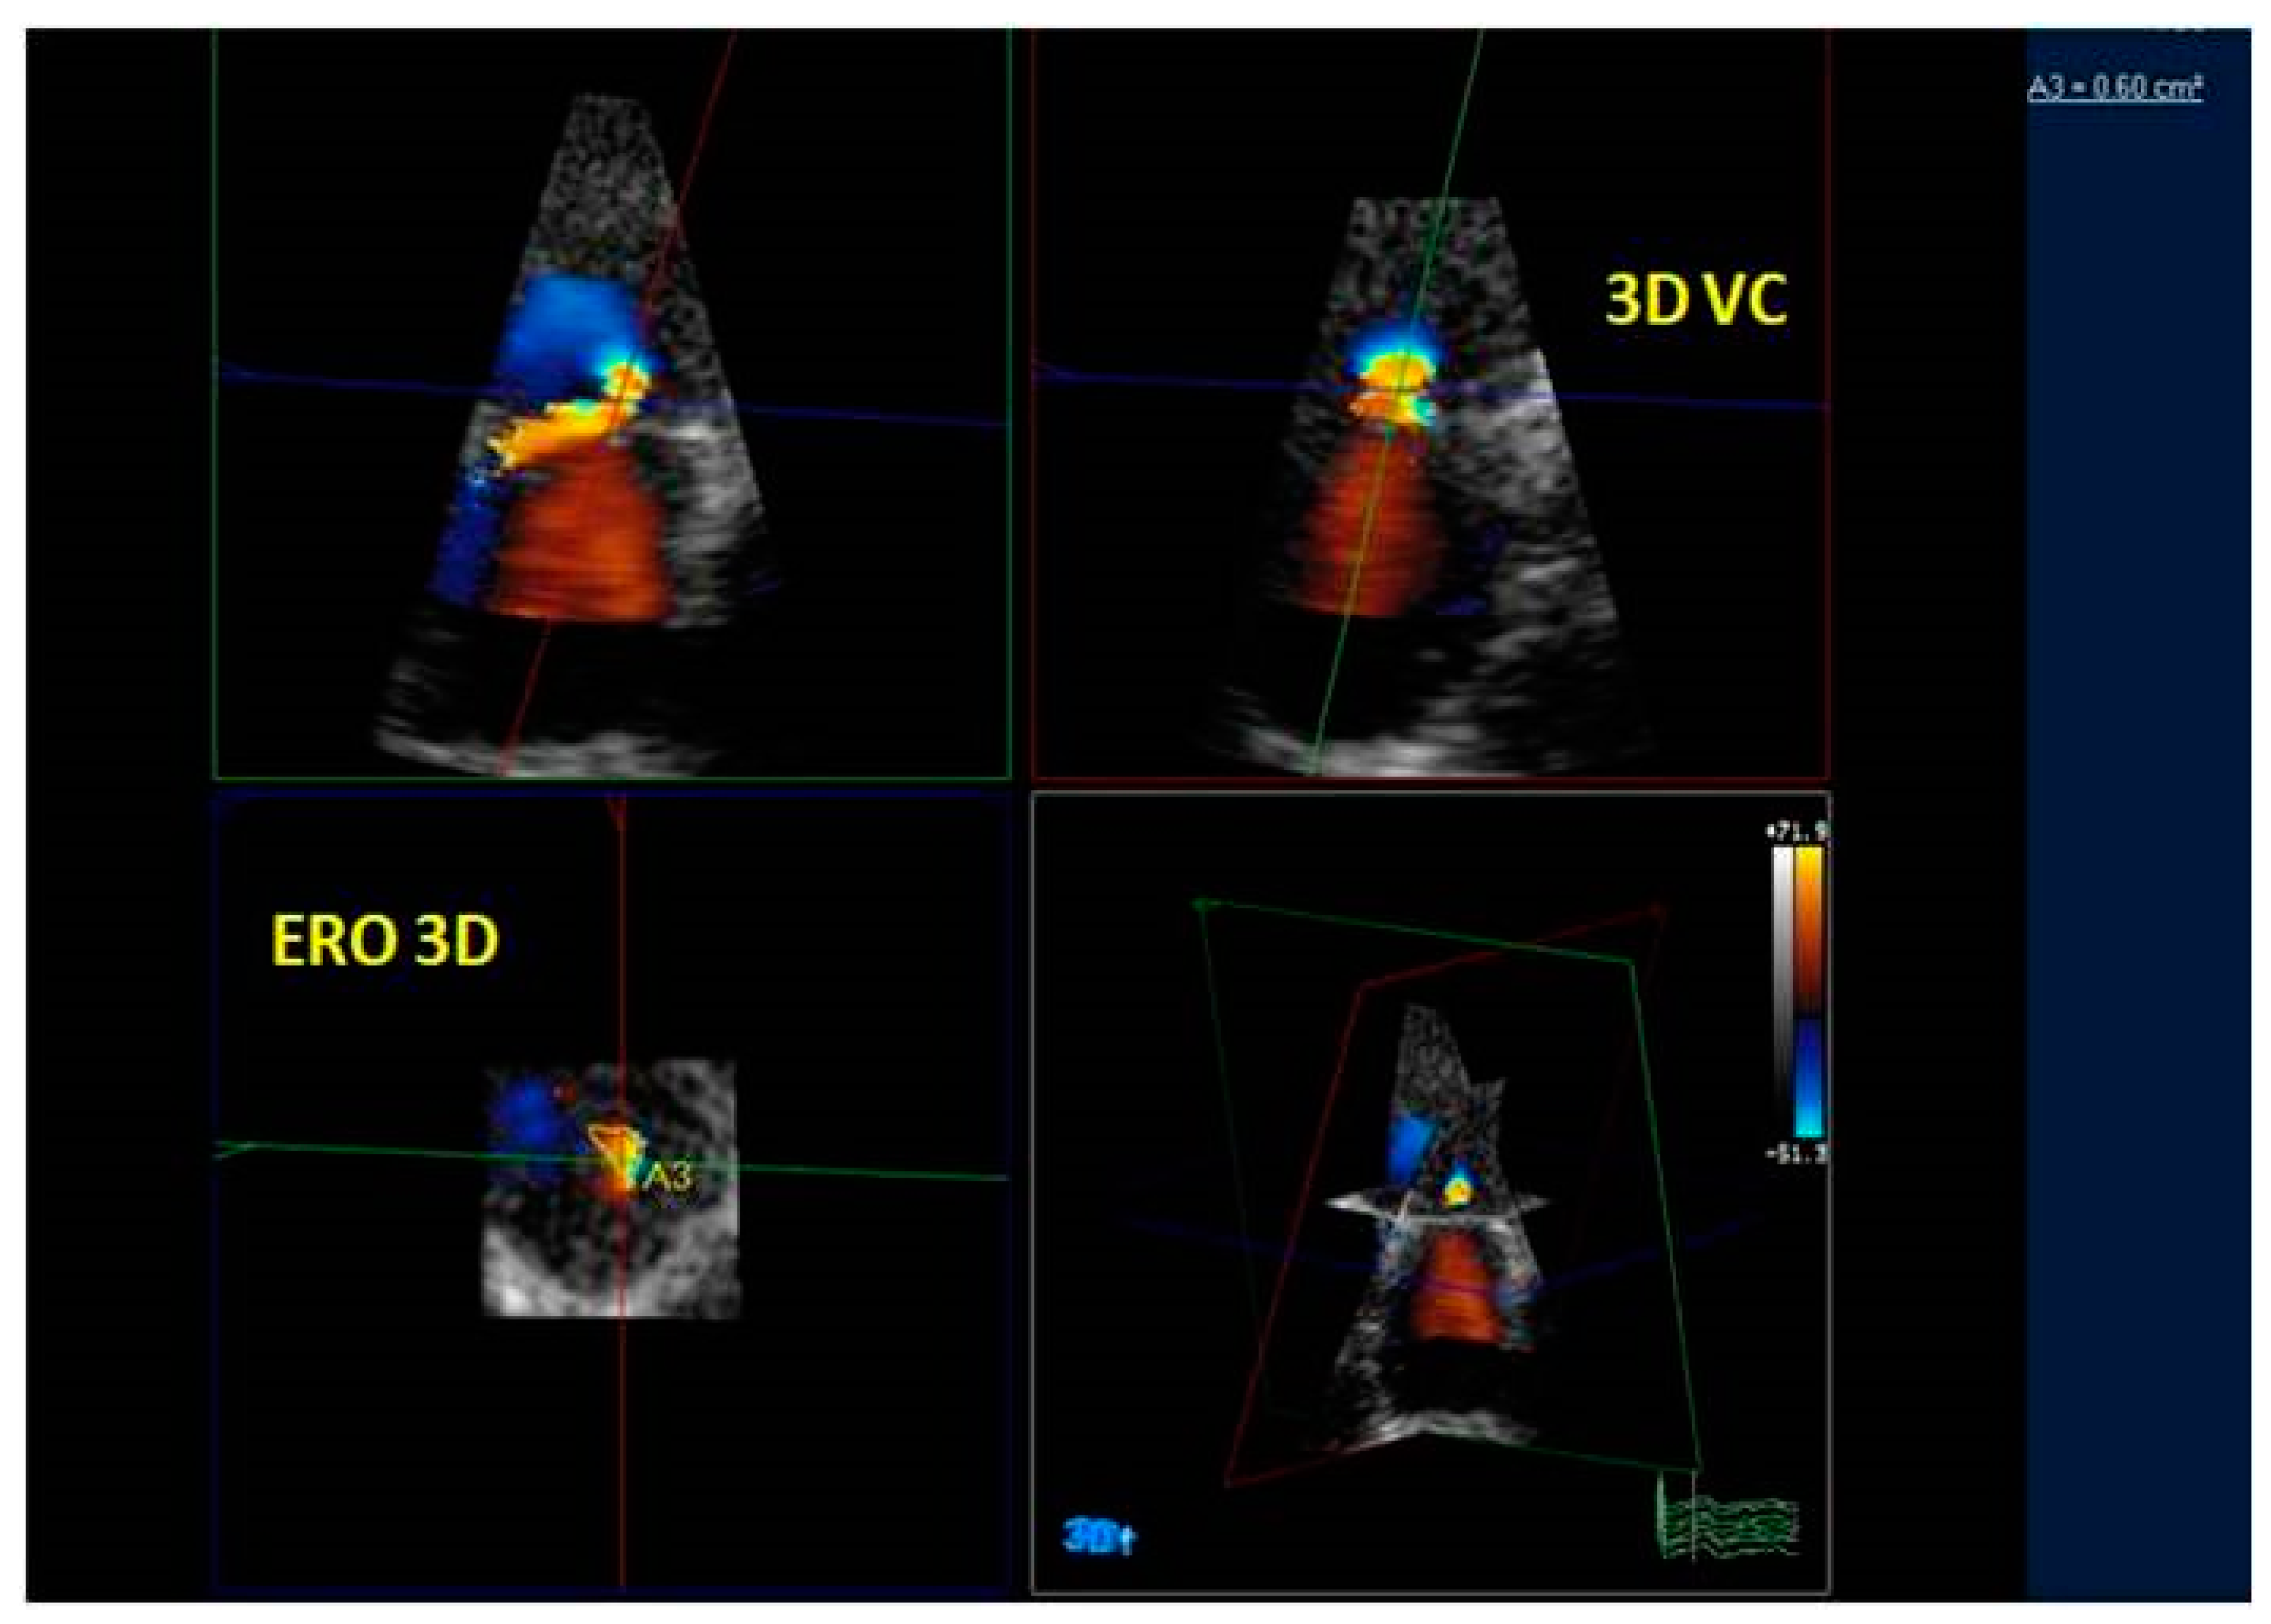

3.3. Quantification of Mitral Regurgitation